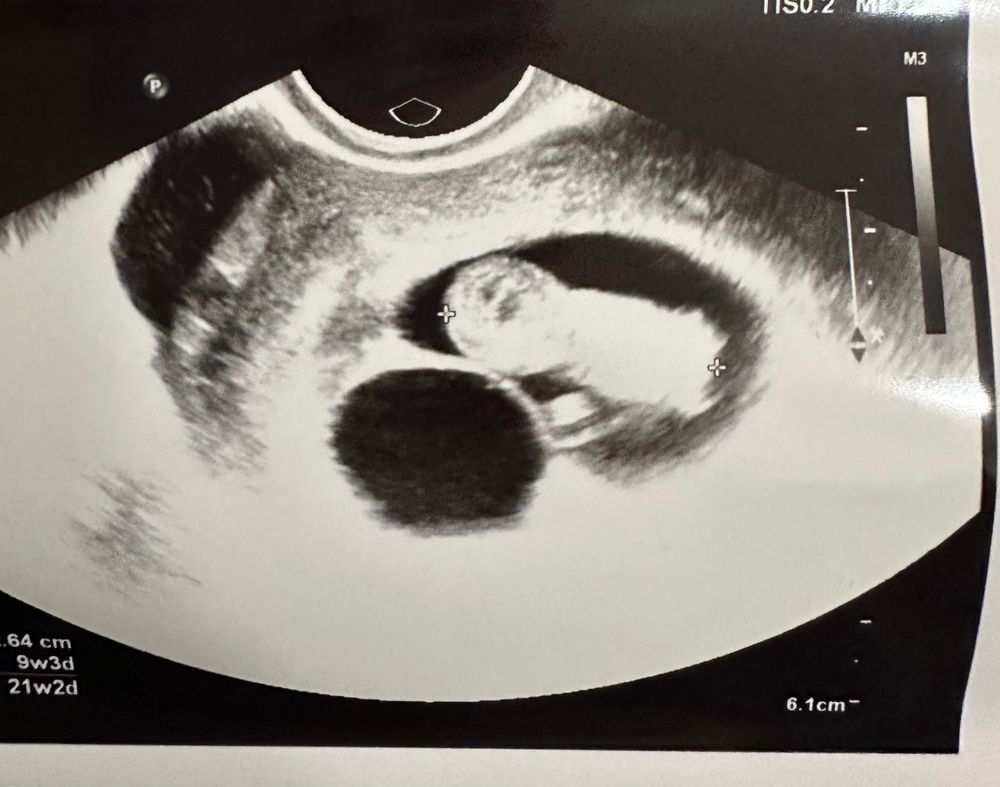

УЗИ сегодня: ктр 27, ПЯ 37*45. Фото:

Это же какой ракурс и срез выбрали в первом случае? Как так можно мерить?

Врач сказала, что со вчерашней узисткой работают только по скорой. Сегодня узи делал мужчина, сказал, что вопросов у него нет к беременности, все хорошо🙏🏼